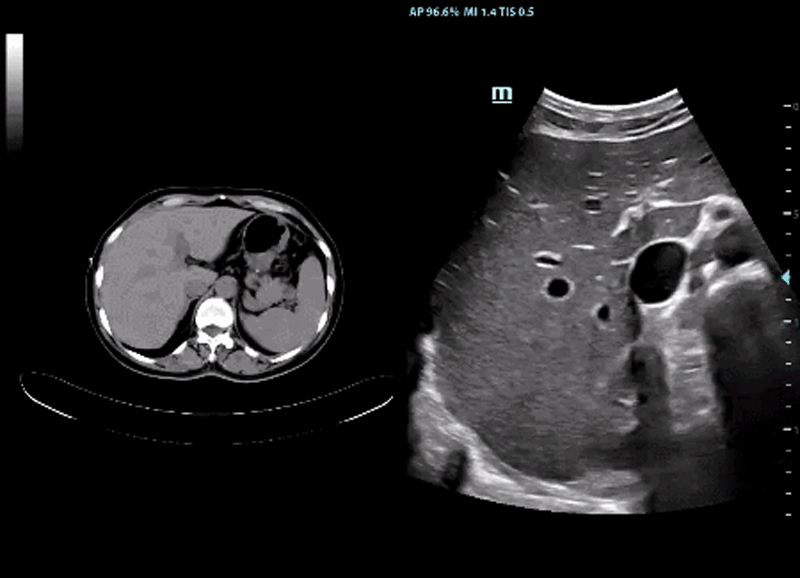

Apart from this, to bring the precision imaging to a new level, DC-80 with X-Insight applies iFusion for accurate volume navigation by CT/MRI and combines with CEUS for easy definition of benign or malignant lesions. It is further supported by a sensitive magnetic motion sensor with millimeter accuracy which can help eliminate the matching distortion and fusion inaccuracy caused by unavoidable patient respiration. As a result, it renders more confidence to ultrasound users on tumor diagnosis and interventional procedure.

iFusion with CEUS